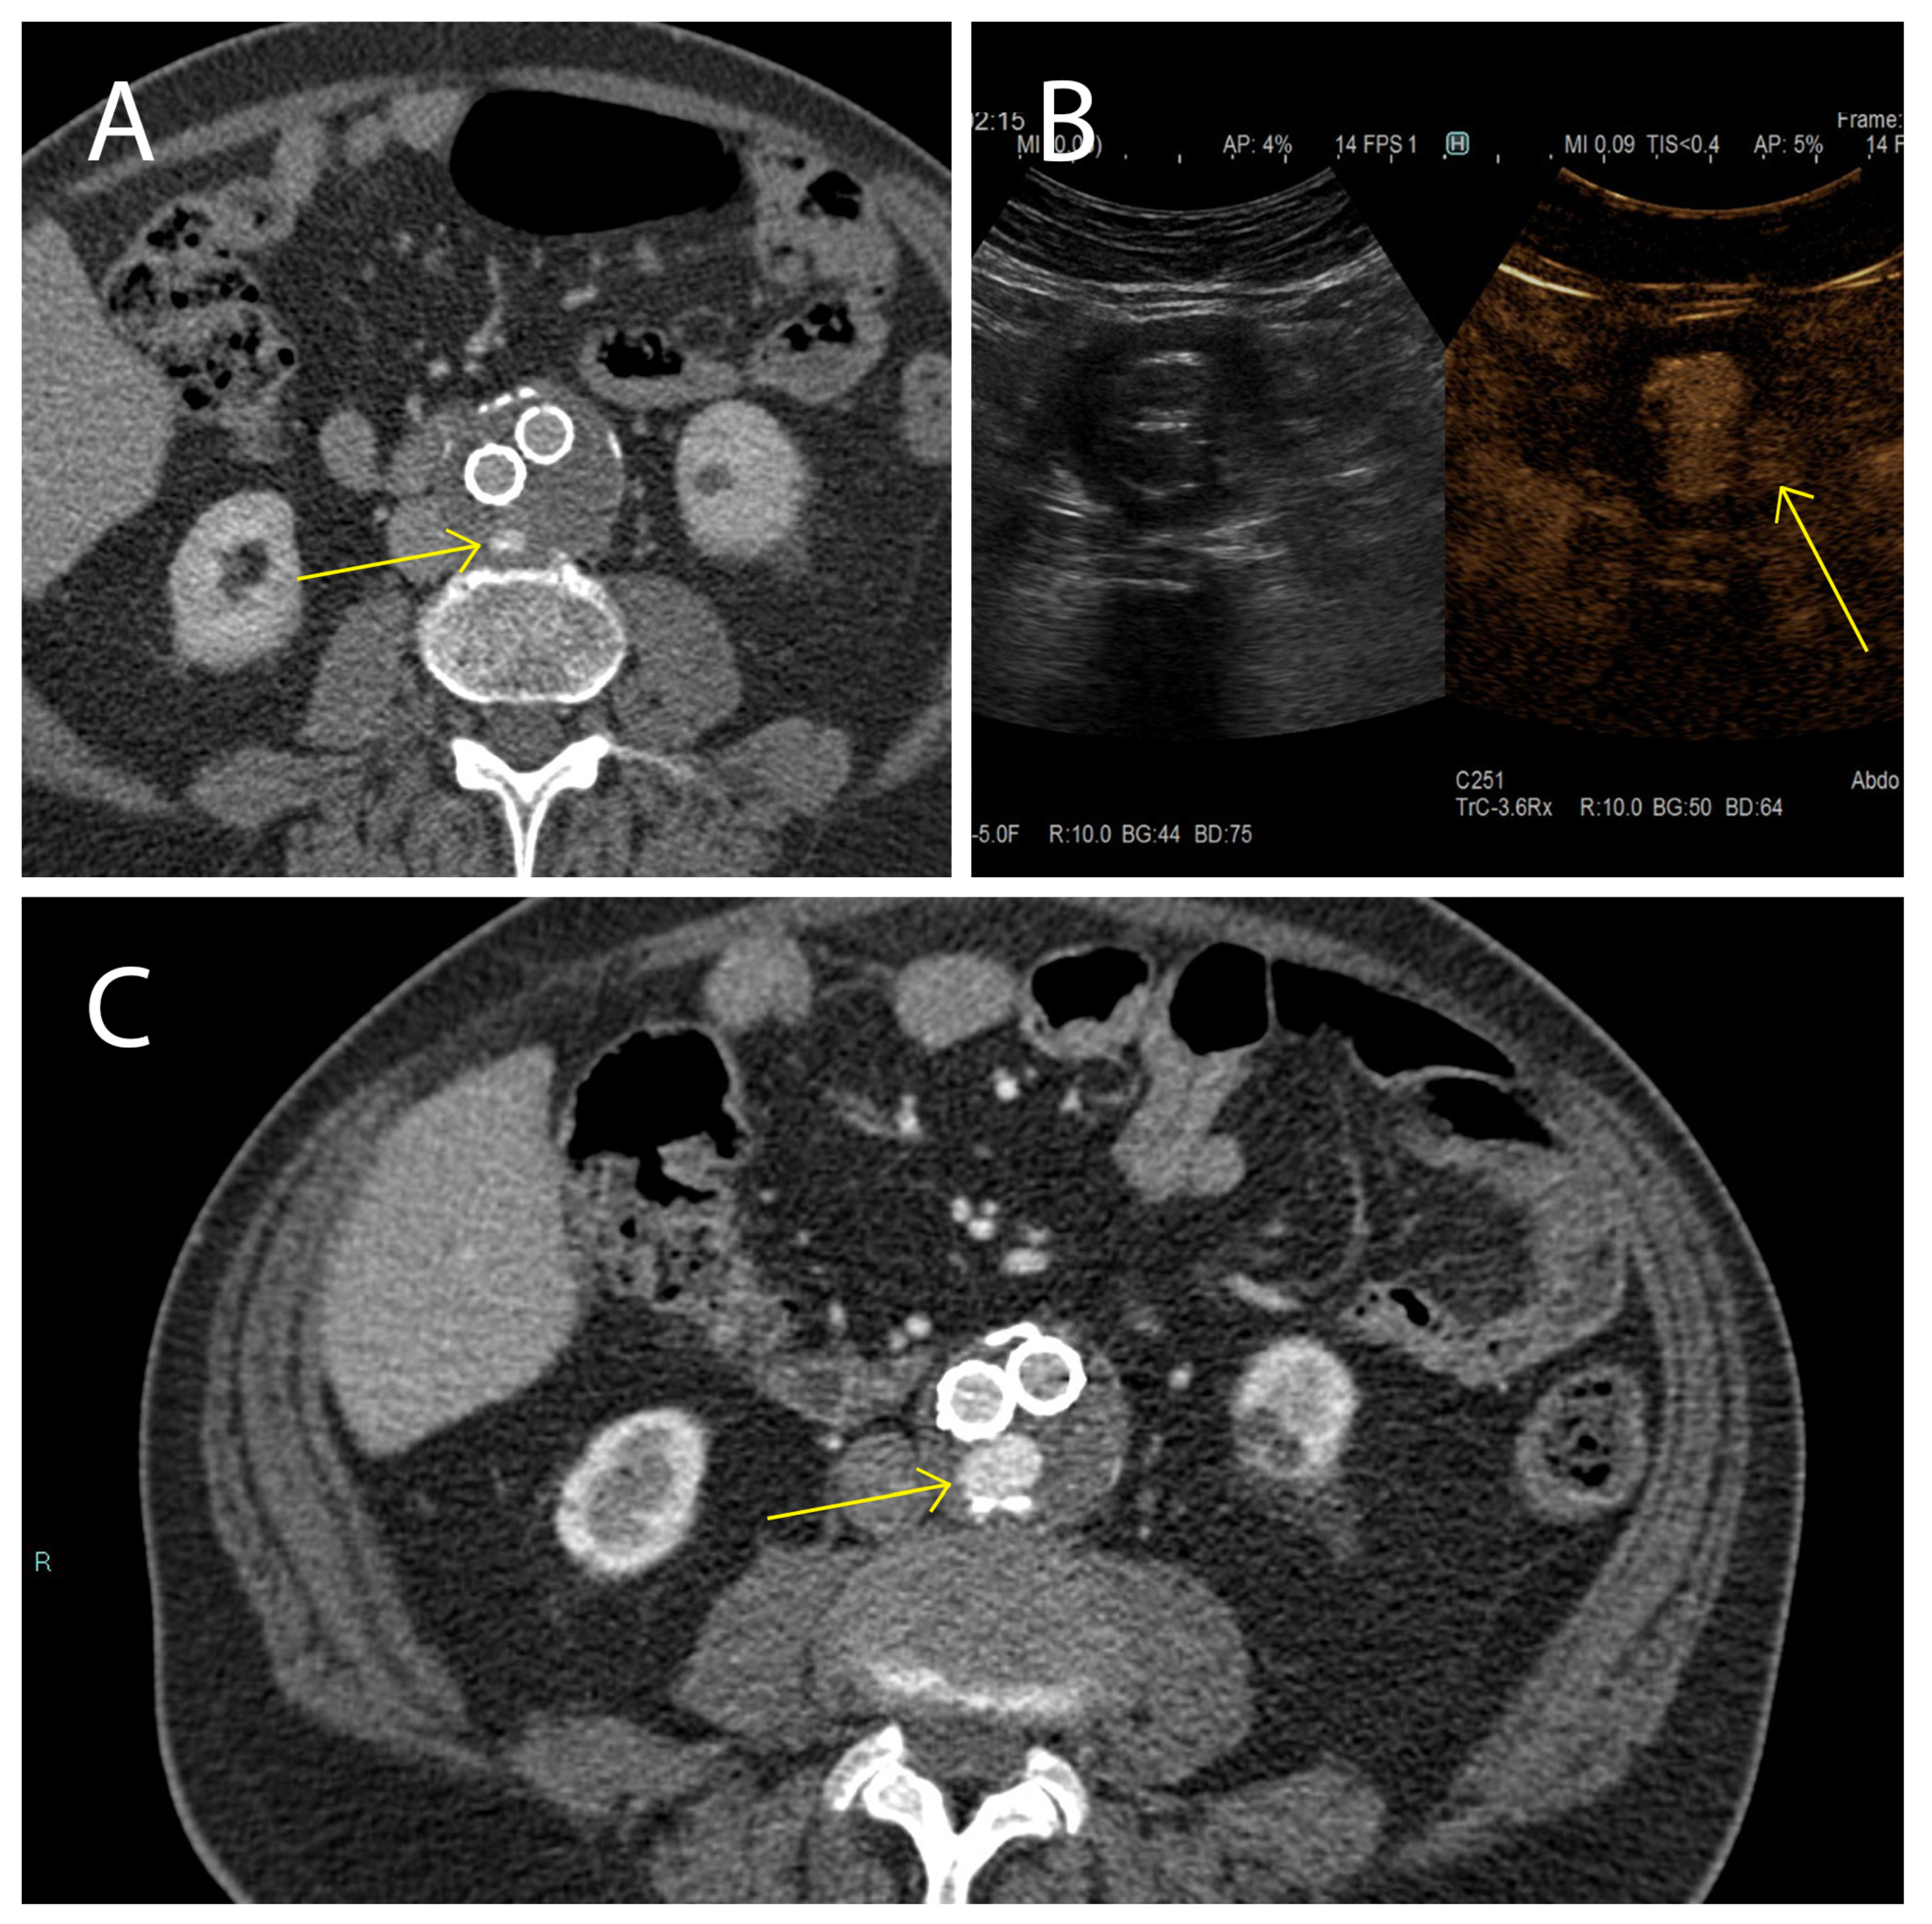

- Serafini, F.L.; Lanuti, P.; Pizzi, A.D.; Procaccini, L.; Villani, M.; Taraschi, A.L.; Pascucci, L.; Mincuzzi, E.; Izzi, J.; Chiacchiaretta, P.; et al. Diagnostic Impact of Radiological Findings and Extracellular Vesicles: Are We Close to Radiovesicolomics? Biology 2021, 10, 1265. [Google Scholar] [CrossRef]